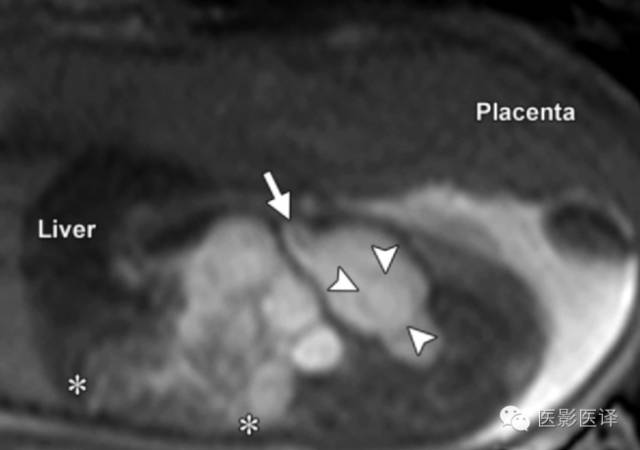

脐尿管囊肿或残留

脐尿管是腹内胚胎尿囊的一部分,它从胎儿膀胱顶延伸至脐部。管状脐尿管通常在孕6周左右退化形成位于正中的脐韧带。当膀胱与脐带插入点的脐尿管闭塞而中份的脐尿管仍然未闭锁时,就会形成脐尿管囊肿。超声显示腹内从膀胱至脐部的一个含液囊肿。脐尿管囊肿仅限于前部中线区,这不同于其他位于后部非中线区的腹内肿块,如卵巢囊肿。MR图像也可用于评价脐尿管残留,中线矢状位常可显示脐尿管。脐尿管囊肿与膀胱相通有助于证实脐尿管未闭(图12/13)。膀胱出口阻塞可能会导致脐尿管永久性开放,可以为膀胱减压。脐尿管囊肿也可与脐带囊肿相通,征象通常很明显。确诊后,建议影像随访。如有感染或恶变倾向,应该进行生后的手术切除。外科干预后,病人的预后非常好。

图13.脐尿管囊肿。胎儿的超声冠状图像显示膀胱顶部上方一个薄壁脐尿管囊肿(*)。脐尿管囊肿的超声主要表现是脐尿管囊肿与膀胱相通(箭)且从膀胱顶部延伸至脐部,这个表现在矢状位显示最佳(未显示).